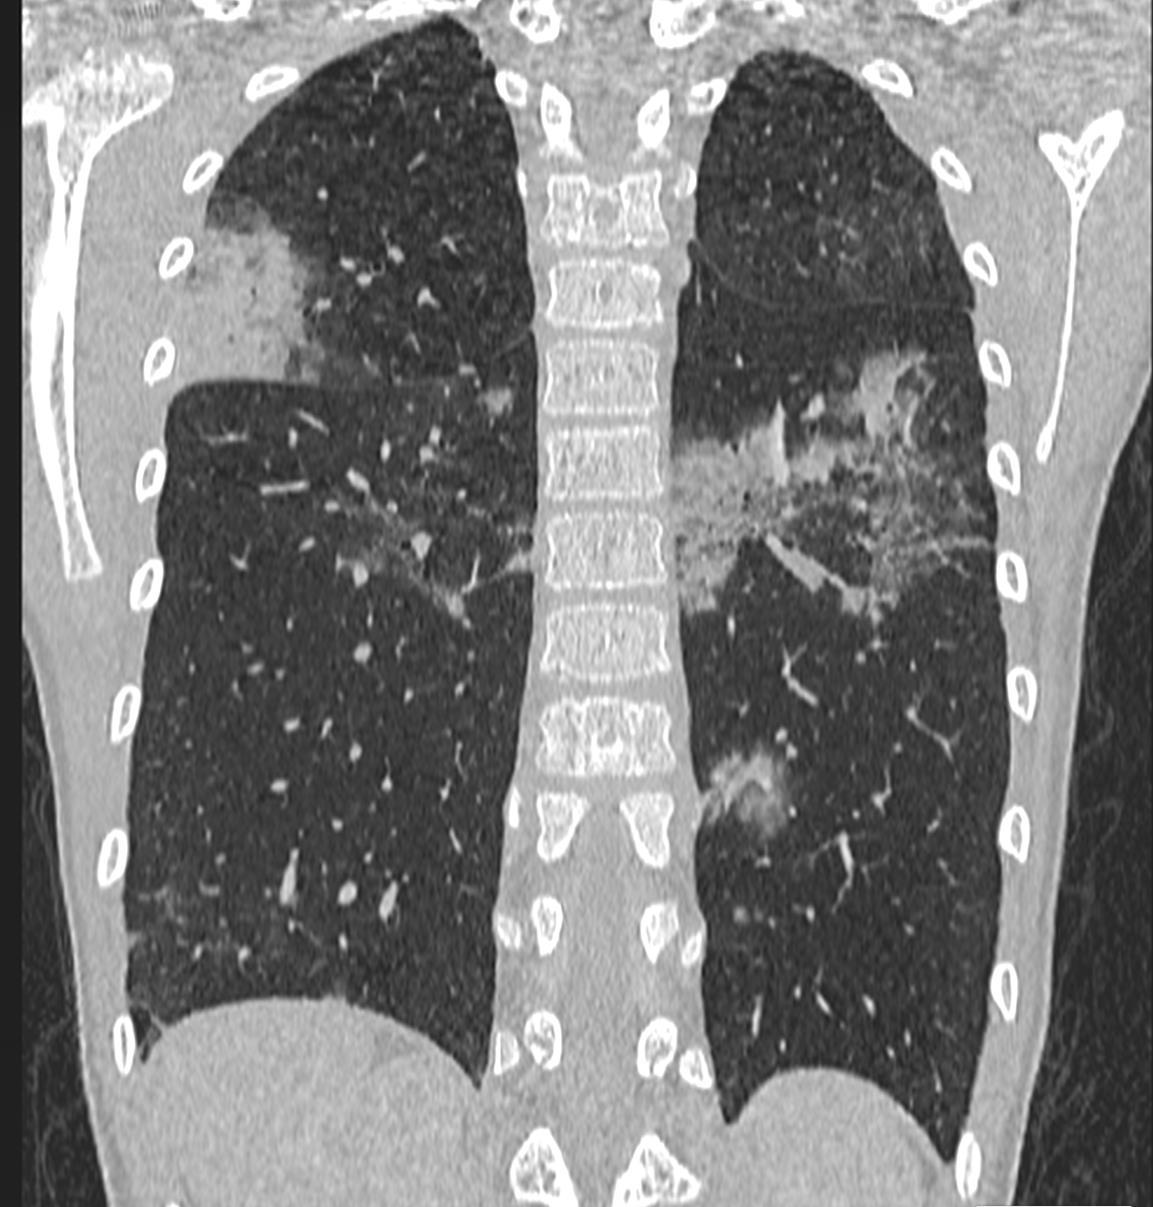

Imaging of Covid 19 infection in children COVID 19 Late

Late

37

Pediatric COVID-19: MIS-C

Thoracic abnormalities

Pulmonary parenchymal abnormalities

Lower lobe atelectasis

Bilateral opacities( ARDS)

Consolidation

Pleural abnormalities

Small pleural effusion